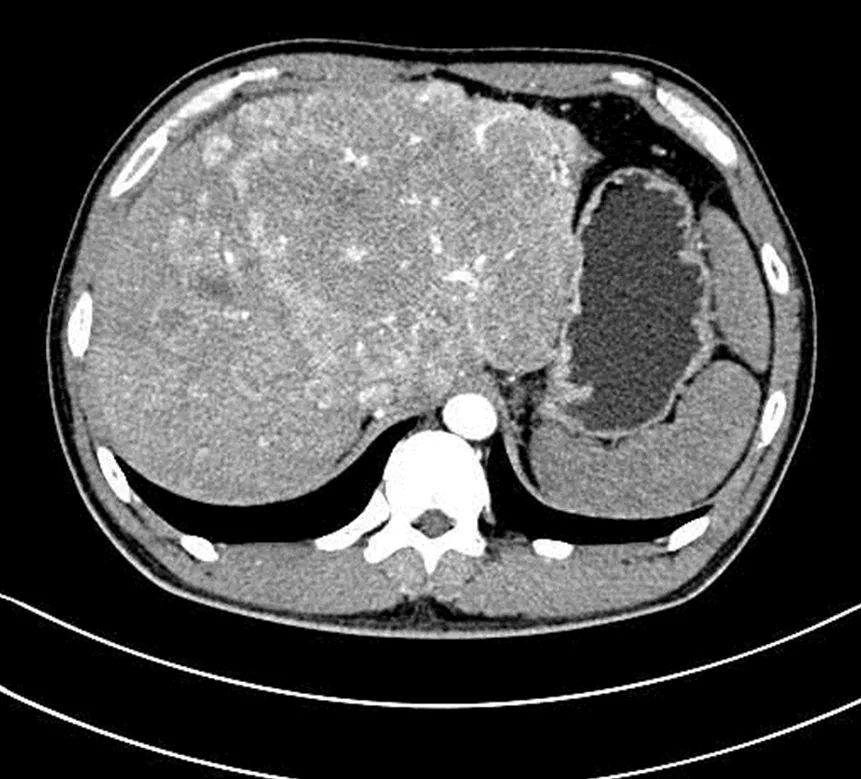

该病例为一名34岁多发巨块型肝癌患者,肝内见一个巨大肿瘤病灶及多发转移病灶。肝内巨大病灶压迫胃部,导致患者进食差,少许进食即饱腹感明显,腹痛,生活质量差。

阳西总医院人民医院肿瘤科成功为患者进行了肝动脉灌注化疗(HAIC)。HAIC疗法经股动脉将微导管置于肝肿瘤分支血管,通过微导管将抗肿瘤药物直接送达肝内肿瘤血管达到治疗目的。经过1个周期的治疗,患者肝部肿瘤较前明显缩小,对胃的压迫减轻,已能正常进食,腹痛腹胀消失,再经过2个周期的HAIC治疗后,肝内巨大肿瘤染色基本消退。